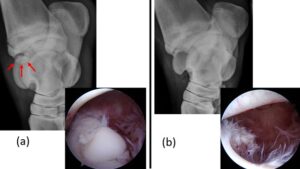

Common clinical conditions that are assessed and treated with arthroscopy include: osteochondritis dissecans (OCD), cartilage lesions, synovitis, and intra-articular injuries such as bone fragments and fractures of the joint. Joint wounds and infections often receive arthroscopic assessment and lavage as a part of treatment. Arthroscopy also serves as a valuable diagnostic tool for evaluating joint abnormalities through direct visualization of cartilage and intra-articular structures. This information can guide both intraoperative and post-operative treatment and help determine prognosis.

Arthroscopic Surgery: Small incisions, known as portals, are made in the skin overlying the joint to be examined or treated. The arthroscopic camera provides real-time visualization of the joint structures on a monitor. The surgeon systematically evaluates the joint synovial lining, cartilage, and tendons and ligaments for abnormalities. Based on the findings, additional portals may be created to allow access for specialized instruments for debridement, fragment removal and joint lavage. The skin incisions are closed with sutures, the joint is bandaged, and the horse is recovered from anesthesia.